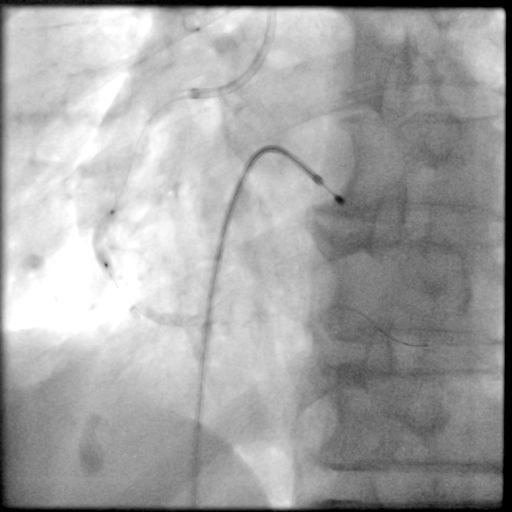

PCI过程-冠状动脉旋切(轨道旋磨)术-3

共计旋切170秒,术后,狭窄较前减轻

PCI过程-球囊PTCA

非顺应性球囊2.75X15mm、3.0X15mm,于RCA中段病变处以12-18atm反复扩张,球囊膨胀不佳。